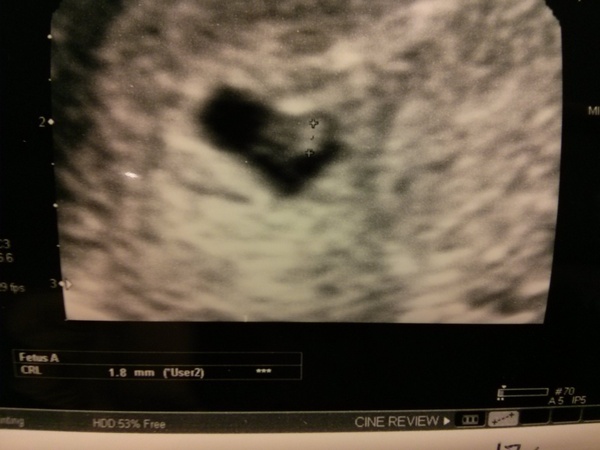

I think we are ok! I told the obstetrician I was 6+6 going from LMP but I didn't think I'd ov'ed until CD18. She did an abdominal scan but was having trouble seeing anything so got in the super experienced sonographer who did an internal dildocam and found the yolk sac straight away and a teeny tiny 1.8mm fetal pole. They said that it all looked good and matched with the dates I thought. They said they wouldn't expect to see a heartbeat until it is at least 7mm (and it should now grow about 1mm everyday), but possibly not even then so they have booked me in for another scan 2 weeks today when I should be about 8 weeks. They said the brown spotting is probably harmless and as far as they could see at this stage everything looked ok, but obviously couldn't give me any guarantees. So please all keep sending your positive thoughts!